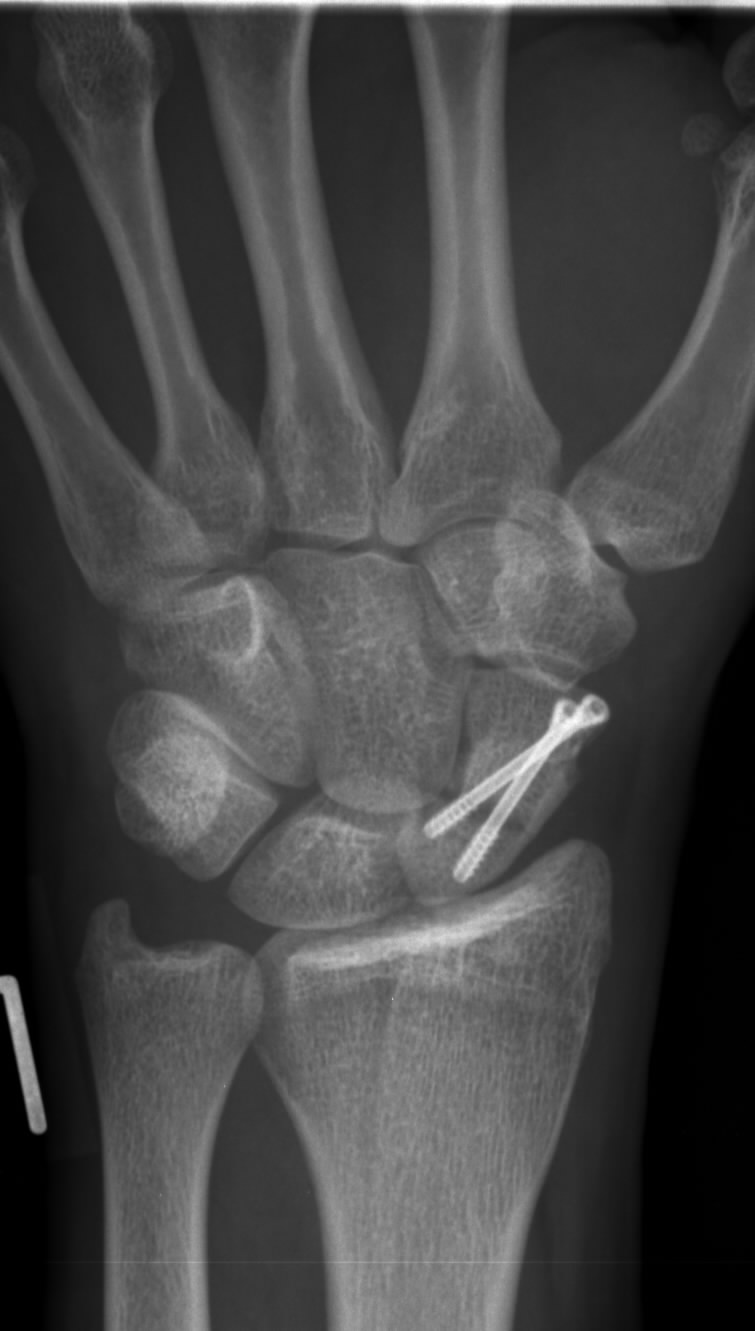

Handwurzelknochen Fraktur

Kahnbeinbruch Fraktur Des Kahnbeins Ursachen Symptome